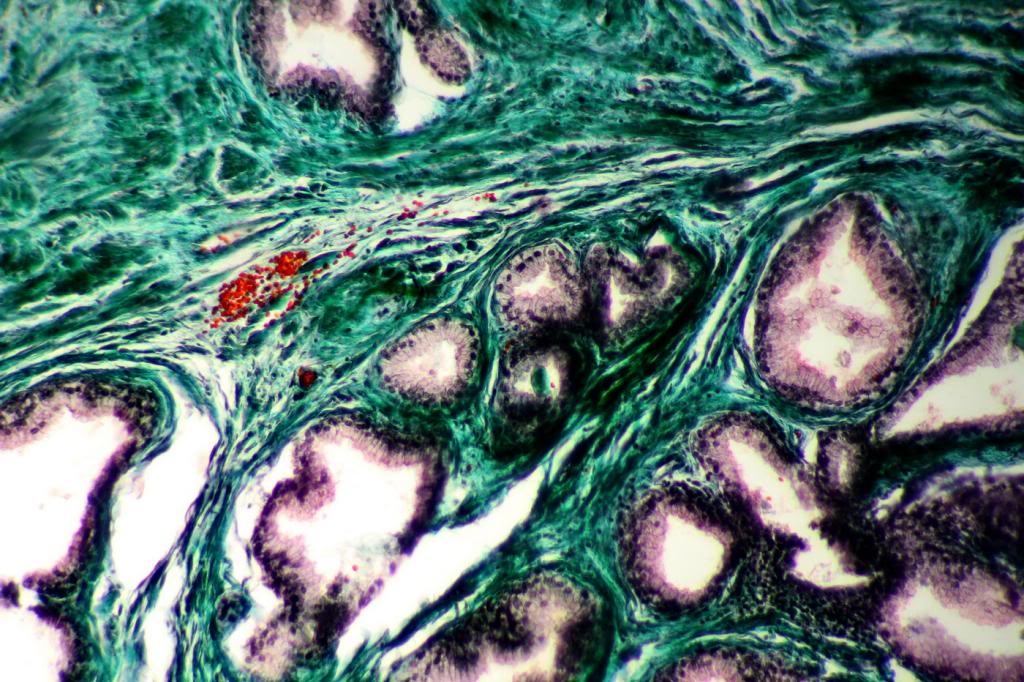

ich bin vor kurzer Zeit an ein Novex (s. https://www.mikroskopie-forum.de/index.php?topic=18401.0) Mikroskop gekommen mit scheinbar funktionstüchtiger Fotoadaption. Mich hat es jetzt mal gereizt, wieweit man mikrofotografisch mit einer "Billiglösung" kommen kann. Neben dem Mikrometer habe ich mal zu den erst besten Präparaten gegriffen (1: beschriftet: Prostata massou goldner; 2: Schmelze Aluminiumoxid). Der Originalfotoadapter von Novex liess sich via T2-Anschluss/-Kameraadapter direkt mit meiner EOS 600D verbinden. Bei den ersten Probeaufnahmen zeigte sich, dass das Auslösen an der Kamera selbst wenig zielführend ist (und bei Objektiven > 10x zu Verwacklungen führt). Aus dem Grund wurden die EOS wie gewohnt mit dem PC verbunden. Die Grenzen der Optik liegen auf der Hand (s. Mikrometeraufnahmen), für allgemeine(re) Zwecke und angesichts des Preises ist die Lösung vertretbar.

Das Meiji-Objektiv kam deshalb zum Zuge, weil das Original Novex 40/0.65 defekt ist.